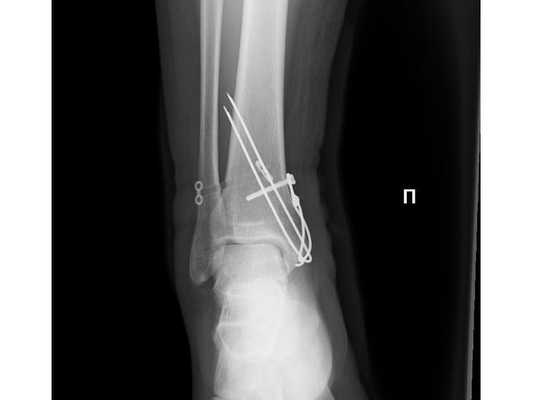

После обследования и уменьшения отёка мягких тканей на четвёртые сутки с момента травмы больному проведено оперативное вмешательство. Под спинномозговой анестезией выполнена открытая репозиция перелома внутренней лодыжки правой голени спицами и стягивающей проволочной петлёй, фиксация дистального межберцового синдесмоза стягивающей петлёй с упорными металлическими площадками.

Ранний послеоперационный период протекал без осложнений. На третьи сутки после операции конечность фиксирована гипсовой повязкой от нижней трети правого бедра до плюснефаланговых суставов. Пациент активизирован с опорой на костыли без нагрузки на правую нижнюю конечность. Выписан на амбулаторное долечивание под наблюдение районного травмпункта.

- Ходьба с опорой на костыли без нагрузки на правую нижнюю конечность в течение 6-8 недель с момента операции.

- Гипсовая иммобилизация правой нижней конечности в течение 6-8 недель.

- Рентгенография правого голеностопного сустава через 4, 8, 12 недель с момента операции.